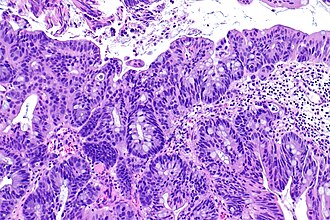

Microscopic

Features:

- Nuclear pleomorphism - may be mild.

- Usually glandular differentiation (most common).

- Frequently looks just like colorectal adenocarcinoma.

- Without urothelial differentiation - essential.[3]

- +/-Evidence of invasion such as:

- Desmoplastic stroma.

- Extensive disordered or cribriform growth.

Subtypes:[2]

- Glandular.

- Papillary.

- Colloidal (mucinous).

- Signet ring cell carcinoma.

- Clear cell carcinoma (also mesonephroid carcinoma).